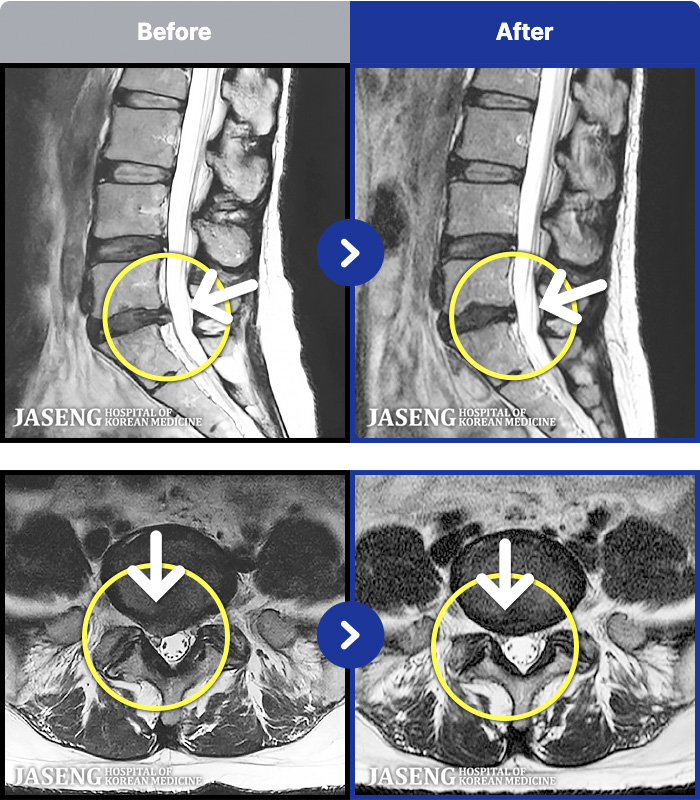

1,286 MRI ũ ʸ Ȯϼ.

ȯںп Ǹ ǿ ԿǾ, ο ġ ۿ Ƿ ġḦ Ͻñ ٶϴ.